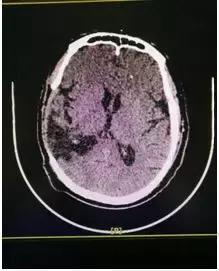

1.术前颅骨巨大缺损

2.术后修补效果